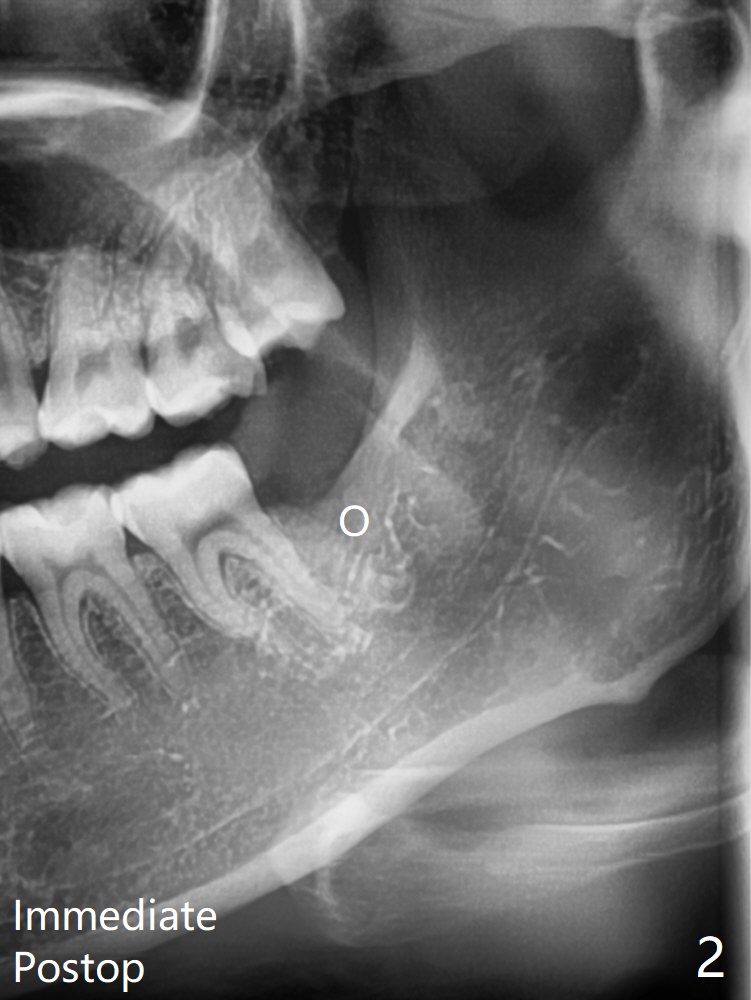

A 23-year-old woman requests #17 extraction because of pain as related to late night lactation (Fig.1 (food <)). The tooth is removed with buccal trough and sectioning (avoiding mesial elevation as much as possible). Osteogen plug is placed against the mesial wall of the socket (horizontal placement, Fig.2).